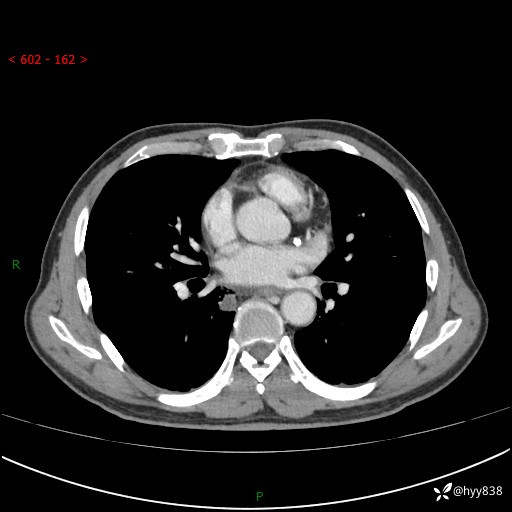

69岁/男,发现肺部病变6天。该有的征象都有,肉芽肿 VS 肿瘤,一念之间---(有结果)

主诉:发现肺部病变6天。

现病史:患者6天前于我院泌尿外科住院,住院期间行胸部CT检查,提示“肺部病变”,患者无畏寒、发热、盗汗、咳嗽、咳痰、咯血、胸痛、呼吸困难,无反酸、腹痛、腹泻、头痛、头晕等不适。未予特殊处理,现为进一步诊治,门诊以“肺肿物”收入我科。 患者本次起病以来,精神食欲尚可,大小便正常,体力及体重无明显变化。

胸部CT平扫+增强